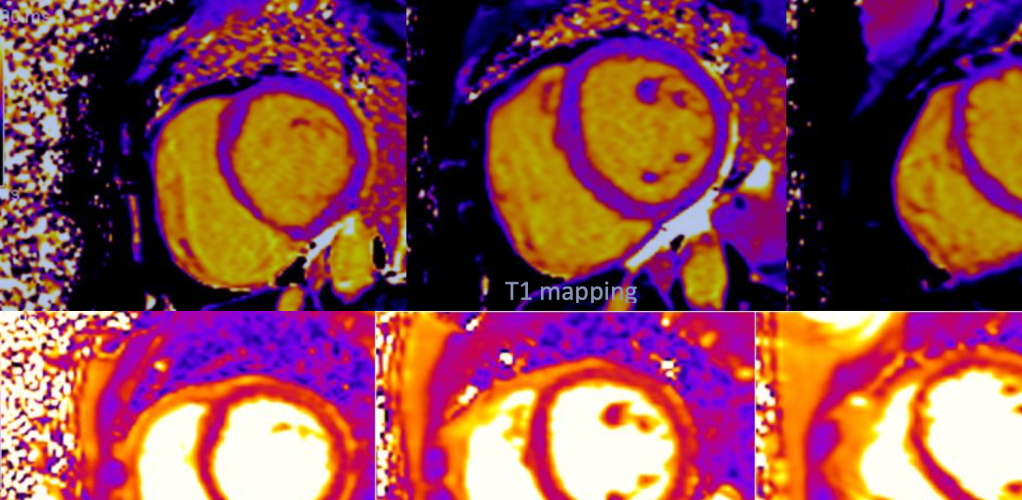

Something wasn’t right, and I continued to have erratic heart rhythms for several months. Finally, a little more than a year after Clay’s death, I was diagnosed with a very rare immune condition affecting my heart and lungs. The reporting cardiologist would never know how perceptive he sounded, in a poetic sort of way, as he read that first radiology report. “You have scarring on your heart, showing evidence of a significant cardiac event.”

My activity was immediately restricted, and I wasn’t even permitted to climb the stairs too quickly. The risks associated with cardiac sarcoidosis are heart failure or sudden death, so I was on board with whatever they required of me, including the high-dose steroids, immunosuppressants, and multiple heart failure meds I’ve been on for the last 15 months. I also had a very clever device the size of a USB stick implanted which keeps track of my every heartbeat, sending data off to my team of doctors in London through an app on my phone. This little device has left me worry-free about my heart, which is amazing.

The great news is that the treatment is working to reduce the inflammation in my heart, and although the scarring will always be there, my heart function has improved a lot– enough for me to run 12 minutes without stopping. A year ago, climbing the stairs would make me breathless. Sometimes it’s hard looking at photos of my swollen “moon face” from these steroids, or not being able to fit into any of my clothes because of the extra bit around my middle. Even harder, dare I say, is the abstinence from alcohol required by the immunosuppressant therapy. As sad as it sounds, television and the Elastic Waistband became companion comforts during periods of lockdown.